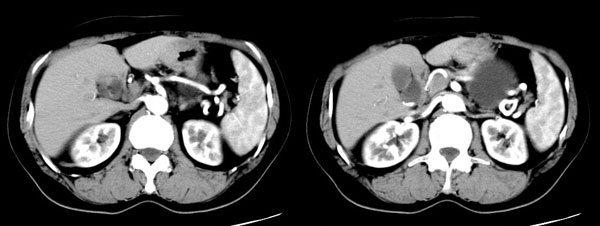

女性,58岁。卵巢癌术后4年余,无不适。体检b超发现左上腹肿块。

ct平扫加增强扫描:胆囊折叠,壁厚,其内见结石。胰腺体尾部见一5.8x7.5cm囊性肿物,ct值12hu,壁薄,增强扫描未明显强化,胰头不大,强化均匀。

ct诊断:1.胆囊炎,胆囊折叠并结石。

2.胰体尾部囊肿。